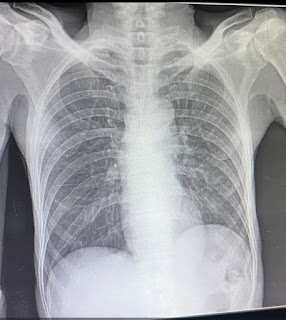

[22-03-2025 11.08] PPM 1: His chest X-ray that made us suspect left diaphragmatic palsy and then look

at his abdomen to find paradoxical respiration.

syn and while this chest X-ray looks very similar, clinically the patient's presentation resembles this